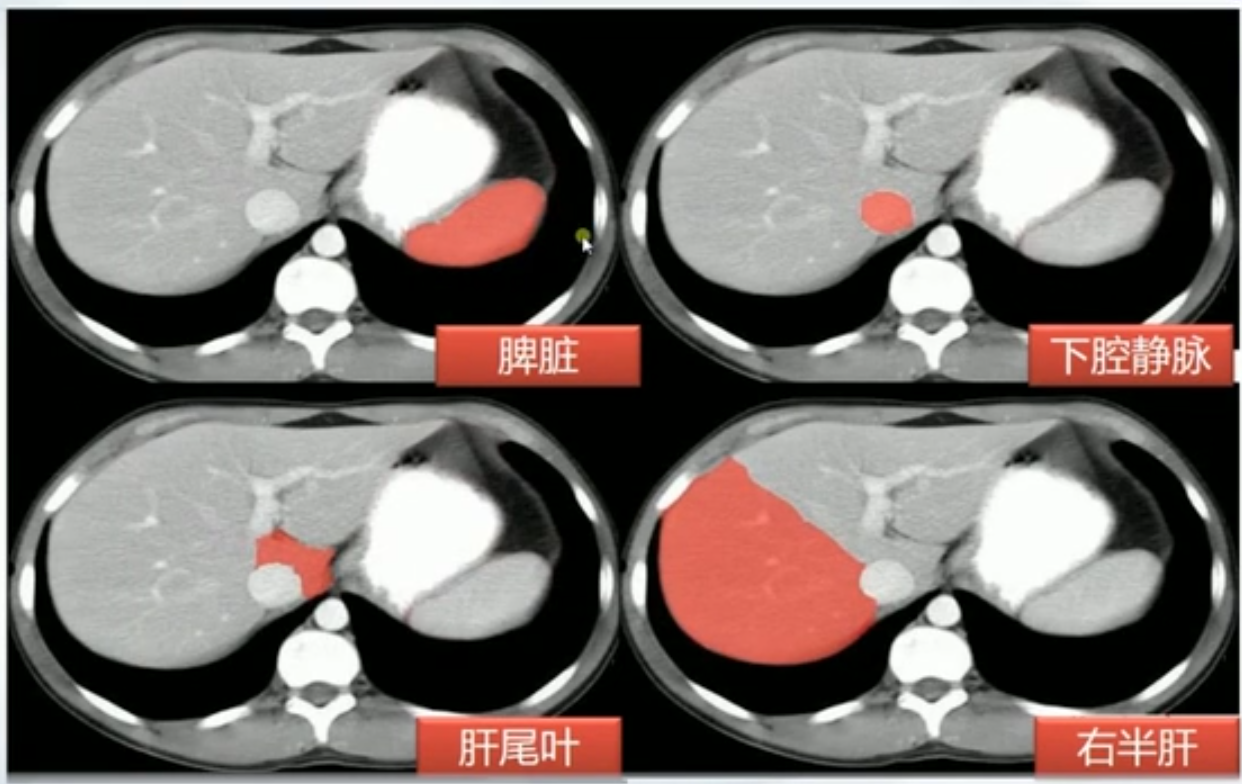

肝CT

- 40~60HU,高于胰,脾

- 肝内管道系统(胆管,肝动脉静脉和门静脉)低于实质,周围小分支多不显示。大血管呈低密度树状影

正常肝重要结构

- 伴随脾脏增大

- 脾脏横向超过5个肋单元

- 纵向看不到肝就应该看不到脾